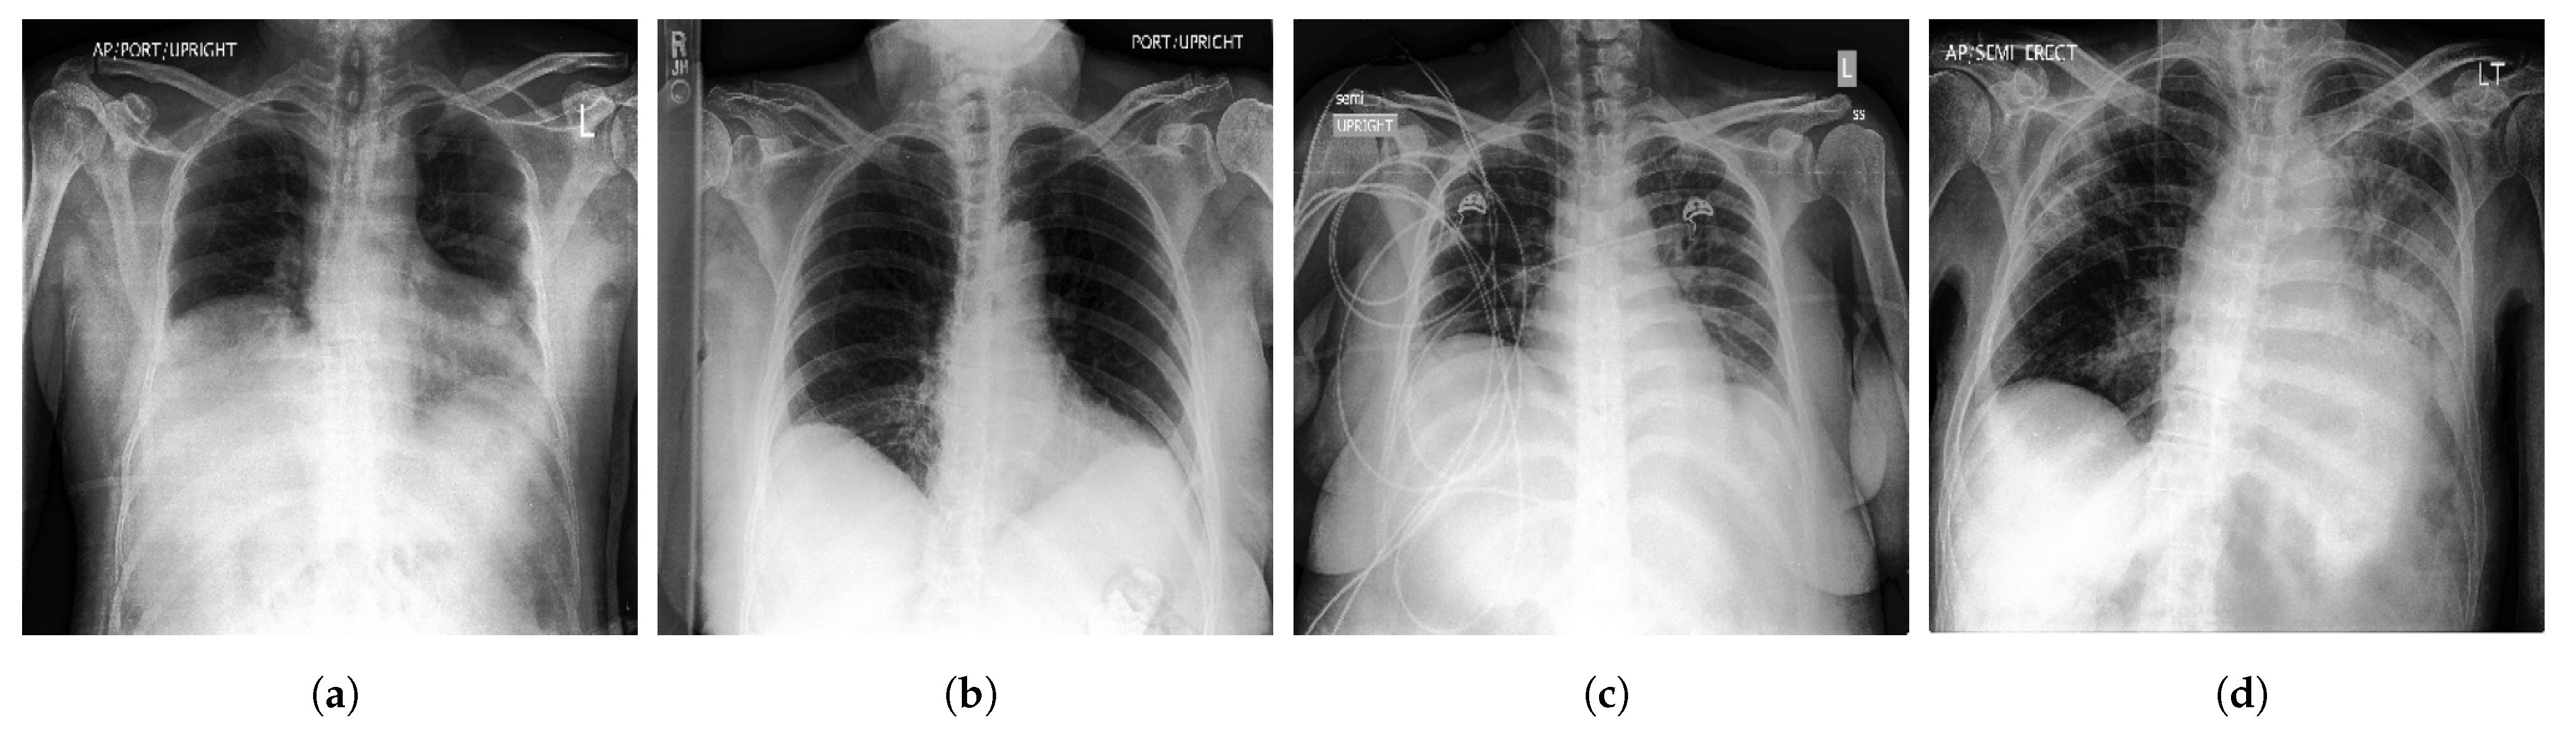

- CheXpert [44] is a large Public dataset of CXR images composed of 224,316 images acquired from 65,240 patients. It contains 14 common chest abnormalities, and it was collected from the Hospital of Stanford between 2002 and 2017. Each image in CheXpert dataset was labeled for the presence of 14 abnormality as negative, positive, or uncertain based on an automated rule-based labeller to extract the observations of experts from the free text radiology reports. Samples of CXR images from CheXpert are shown in Figure 3.

Figure 3.

Samples of CXR images from CheXpert dataset [44] where, (a) Atelectasis; (b) Cardiomegaly; (c) Edema; (d) Pneumonia.

- VinDr-CXR [48] is a public CXR dataset with radiologist-generated annotations. It consists of 18,000 CXR images that come with the location and the classification of the chest diseases. This dataset was collected from two of the biggest hospitals in Vietnam that are Hospital H108 and the HMUH (Hanoi Medical University Hospital) [49]. Figure 4 shows CXR samples from VinDr-CXR dataset.

Figure 4.

Examples of CXR images from VinDr-CXR dataset [48] where, (a) Infiltration; (b) Pleural Effusion; (c) Pneumothorax; (d) Pulmonary Fibrosis.